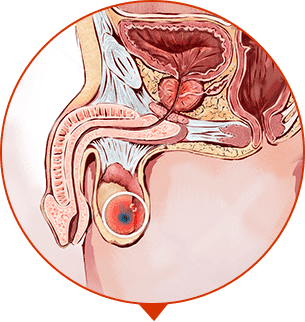

ΚΑΛΟΉΘΗ ΥΠΕΡΠΛΑΣΊΑ ΤΟΥ ΠΡΟΣΤΆΤΗ

Πολλαπλασιασμός του ιστού του προστάτη, σχηματισμός όγκων και "κόμβων"

ΟΓΚΟΛΟΓΙΑ

Κακοήθης όγκος, η πιο κοινή αιτία θανάτου των ανδρών